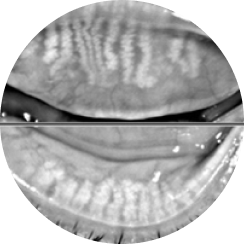

• Slit Lamp Microscopy Examination

Slit Lamp Microscopy Examination

The condition of the cornea is

examined in detail, including the tear film

meibomian gland function

eyelid, and conjunctival inflammation.